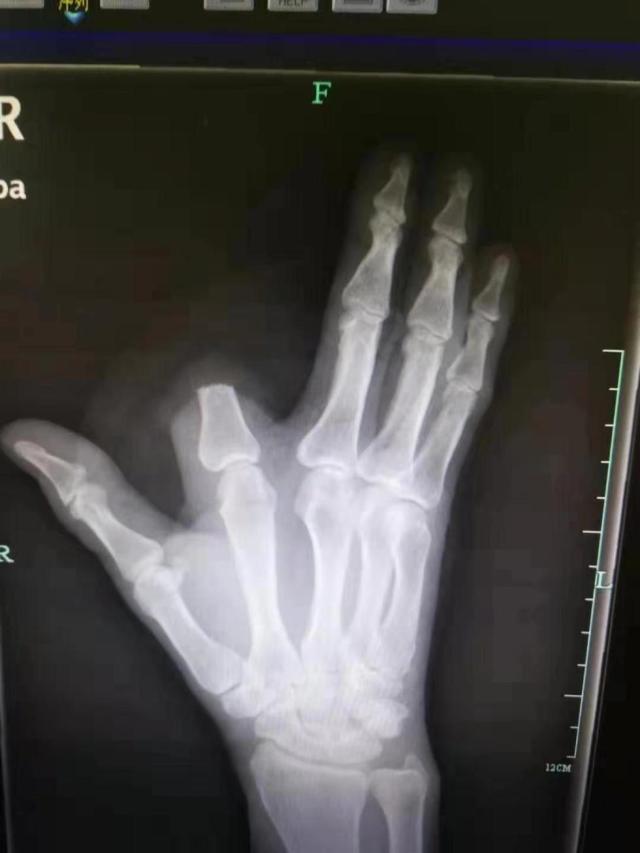

其实单纯从毒性来说,五步蛇的蛇毒并不是很厉害,但是人家的剂量大啊。中国致死率第一的毒蛇不是它,但是说到致残率它可就厉害了,不少人被咬了之后没有及时就医,导致需要进行截肢手术。

由于五步蛇的蛇毒具有溶血性,被它咬伤后,伤口最好不要切开,以免血液不能凝固,导致大量出血,引起贫血等症状。我们可以用手在伤口处挤压排毒,并用清水对伤口进行充分地冲洗。千万别学电视剧里用嘴吸毒,要是嘴巴里有伤口的话,比如空腔溃疡,牙龈出血等等,毒液很容易顺着伤口进入人体的。

我们可以用绳子或者鞋带之类的东西将患肢进行结扎,结扎在靠近心脏的近心端上3-5cm。但一定要注意啊,不能绑太紧,绑太紧的话容易造成肢体组织坏死,别到时候蛇毒没让你截肢,自个把自个弄得截肢了。应当捆绑3-5分钟后进行一定的释放,再接着捆绑3-5分钟。

被五步蛇咬了之后,大家一定要镇定,不要自己吓自己,大部分情况下及时就医是可以治好的,不要心一狠,直接自己就给自己截肢了,那样后悔就来不及了。杭州一男子张先生在山上干活时被毒蛇咬伤了,在发现是五步蛇之后,他居然直接拿刀砍掉了自己一部分的食指。这就可以看出他有多恐惧了,真的是狼人啊,核桃就算是被咬了估计也下不了这手啊。

不过医生提醒,其实被五步蛇咬伤,毒素蔓延至全身需要过程,只要及时就医,通常不会致命。被五步蛇咬伤,并非像传说中那样,走上五步便会毒发身亡。哪怕是毒性猛烈的银环蛇,被咬后只要在6小时内就医,也不会有性命之忧。